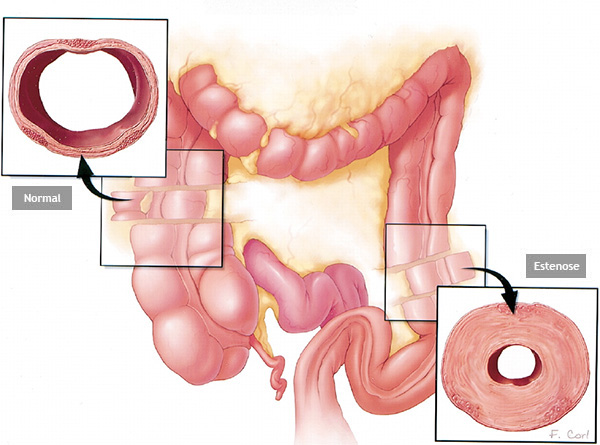

Estenose do intestino

Estenose do intestino é o estreitamento parcial ou total do intestino grosso (ou raramente do intestino delgado) que impede a progressão do conteúdo através do mesmo.

Estenose do intestino pode acontecer por 2 causas principais:

1- Tumores do intestino: alguns tumores do intestino podem crescer ao ponto de causar a obstrução do órgão. Nestes casos geralmente realiza-se cirurgia para se retirar a parte do intestino acometida. Nos casos muito avançados pode-se passar através da colonoscopia uma prótese autoexpansível para desobstrução. Esta prótese também pode ser colocada para melhorar o estado físico e o preparo do paciente antes de ser realizado uma cirurgia definitiva.

2- Estenose benigna: algumas inflamações do intestino podem ao cicatrizar levar a retração da parede do órgão e fechamento do mesmo. Doenças como a Retocolite Ulcerativa, a Doença de Crohn, a Colite por radioterapia, e algumas infecções do intestino podem levar a este processo. Existem também as estenoses pós operatórias que acontecem quando ocorre uma cicatrização exagerada da parede do intestino remanescente após a cirurgia.

Nos casos de estenoses benignas do intestino realiza-se a dilatação endoscópica da região com balão do tipo hidrostático.

Estenose do intestino

Estenose do intestino é o estreitamento parcial ou total do intestino grosso (ou raramente do intestino delgado) que impede a progressão do conteúdo através do mesmo.

Estenose do intestino pode acontecer por 2 causas principais:

1- Tumores do intestino: alguns tumores do intestino podem crescer ao ponto de causar a obstrução do órgão. Nestes casos geralmente realiza-se cirurgia para se retirar a parte do intestino acometida. Nos casos muito avançados pode-se passar através da colonoscopia uma prótese autoexpansível para desobstrução. Esta prótese também pode ser colocada para melhorar o estado físico e o preparo do paciente antes de ser realizado uma cirurgia definitiva.

2- Estenose benigna: algumas inflamações do intestino podem ao cicatrizar levar a retração da parede do órgão e fechamento do mesmo. Doenças como a Retocolite Ulcerativa, a Doença de Crohn, a Colite por radioterapia, e algumas infecções do intestino podem levar a este processo. Existem também as estenoses pós operatórias que acontecem quando ocorre uma cicatrização exagerada da parede do intestino remanescente após a cirurgia.

Nos casos de estenoses benignas do intestino realiza-se a dilatação endoscópica da região com balão do tipo hidrostático.